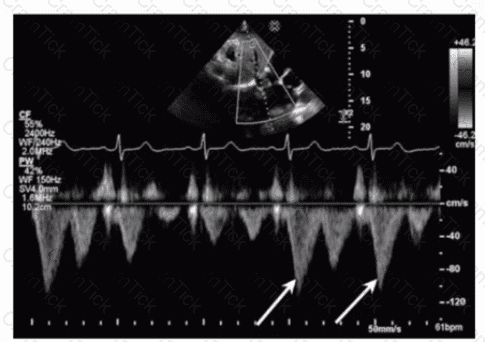

What is the incidental finding seen by color Doppler in this four-chamber view of a patient with left atrial enlargement?